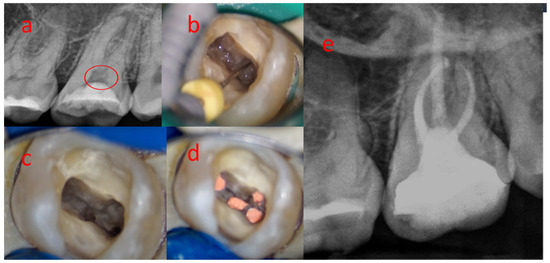

3.1. Sample 01

3.7. Sample 07